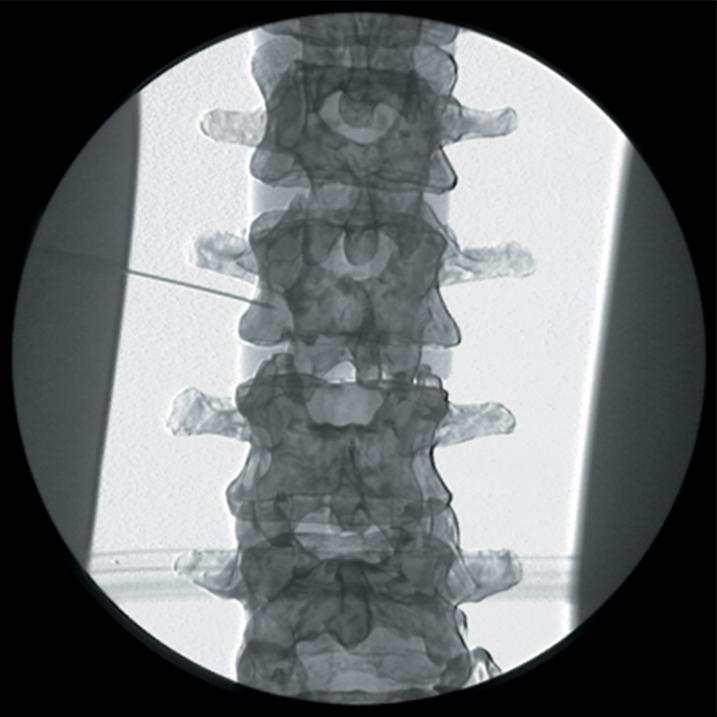

The Regional Anaesthesia Simulation Manikin has been designed by a Consultant Anaesthetist at the Manchester and Salford Pain Centre for training anaesthetists in correct needle placement in Nerve Blocks for pain management.

- Knowledge of surface anatomy applied to the individual nerve blocks

- Orientation of image and identification of appropriate radiographic landmarks

- Identification point of needle insertion and angle of direction

- Recognition of contact with deep bony structures

- Principle of withdrawing and directing needle to alter the angle

- The end point of simulation is the correct radiographic appearance

- The manikin consists of a specially coated plastic human skeleton, head covered in artificial skin and fabric covered torso, on which trainees can practice the placement of needles under X-ray image intensifier control

- The X-ray density of the manikin is low so that the doses of radiation used during simulated procedures are reduced